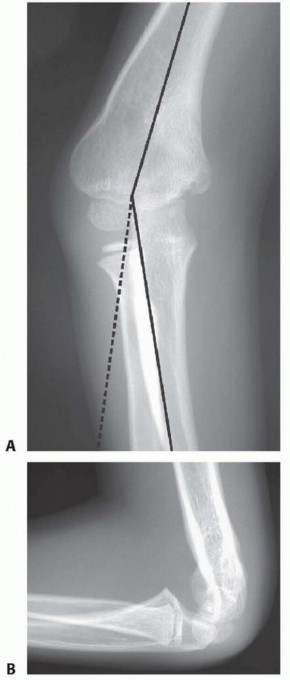

Chapter 15 Supracondylar Humeral Osteotomy for Correction of Cubitus Varus Yi-Meng Yen Richard E. Bowen Norma…